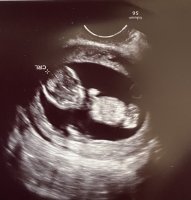

Da har vi vært på ul,og alt ser strålende ut!:D Jeg er så letta!:smug:

Å så ser det (ganske tydelig) ut som det blir en lillebror:joyful:

Kroppen målte til 13+2,akkurat det jeg har går ut fra. Men hodet målte til 13+3,og sønnen jeg har fra før har alltid hatt et stort hode,så det hørtes riktig ut:hilarious::hilarious: